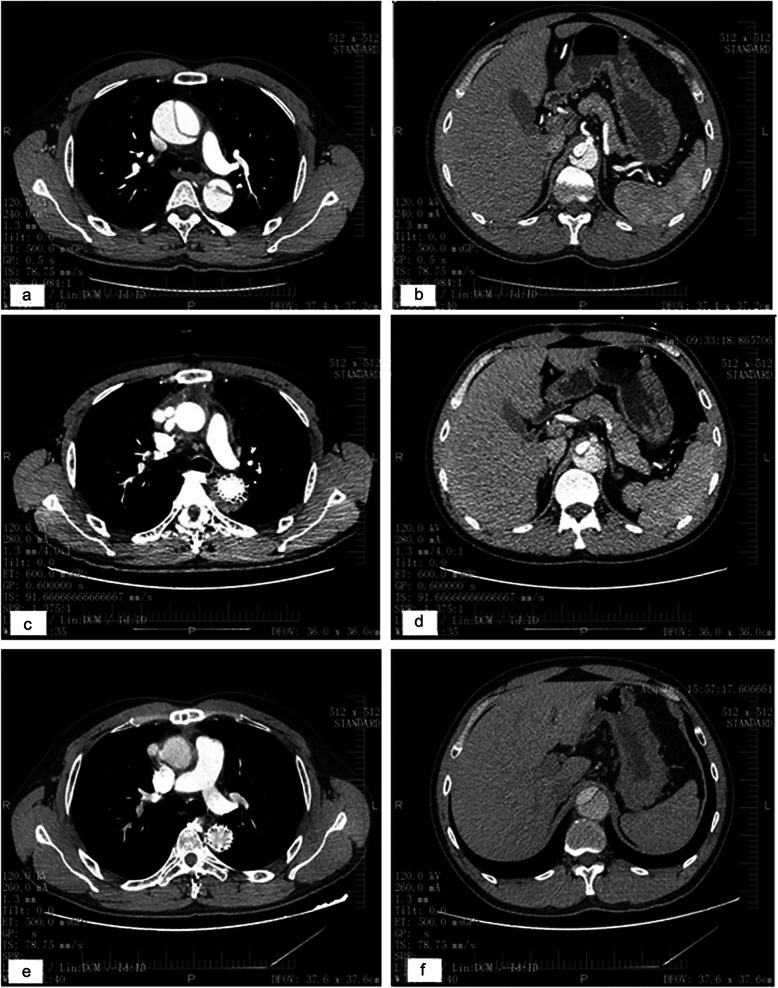

All patients underwent computed tomography. The true lumen was compressed by a huge false lumen before surgery at the carina (Fig. 4a) and celiac artery (Fig. 4b) levels. Thrombosis of the false lumen was observed around the elephant trunk at the carina and celiac artery levels 1 month after the first stage surgery (Fig. 4v). Three months after TEVAR, false lumen thrombosis was resorbed; in addition, the trunk was fully expanded at the carina level, and the true lumen was enlarged at the celiac artery level (Fig. 4e, f).

Fig. 4.

After Stanford A dissection, the true lumen was compressed by a huge false lumen before surgery at the carina (a) and celiac artery (b) levels. Thrombosis of the false lumen was observed around the stented graft at the carina (c) and celiac artery (d) levels 1 month after the first operation. TEVAR was performed and 3 months later, false lumen thrombosis was resorbed; in addition, the elephant trunk was fully expanded at the carina level (e), and the true lumen was enlarged at the celiac artery level (f)

The aortic data at the celiac artery level are displayed in Table 3. The true lumen was not enlarged enough after the first surgery. After TEVAR, substantial improvement was noted. The true lumen index increased to 56.8 ± 10.9% (P < 0.05 compared to the value after the first surgery).